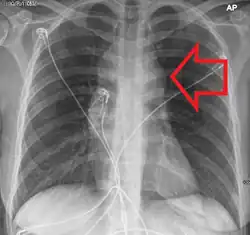

TdT, CD2, CD7

It often presents as a mediastinal mass because of involvement of the thymus. It is highly associated with NOTCH1 mutations, and is most common in adolescent males.

Most common in young adults, often arises in the mediastinum or cervical lymph nodes